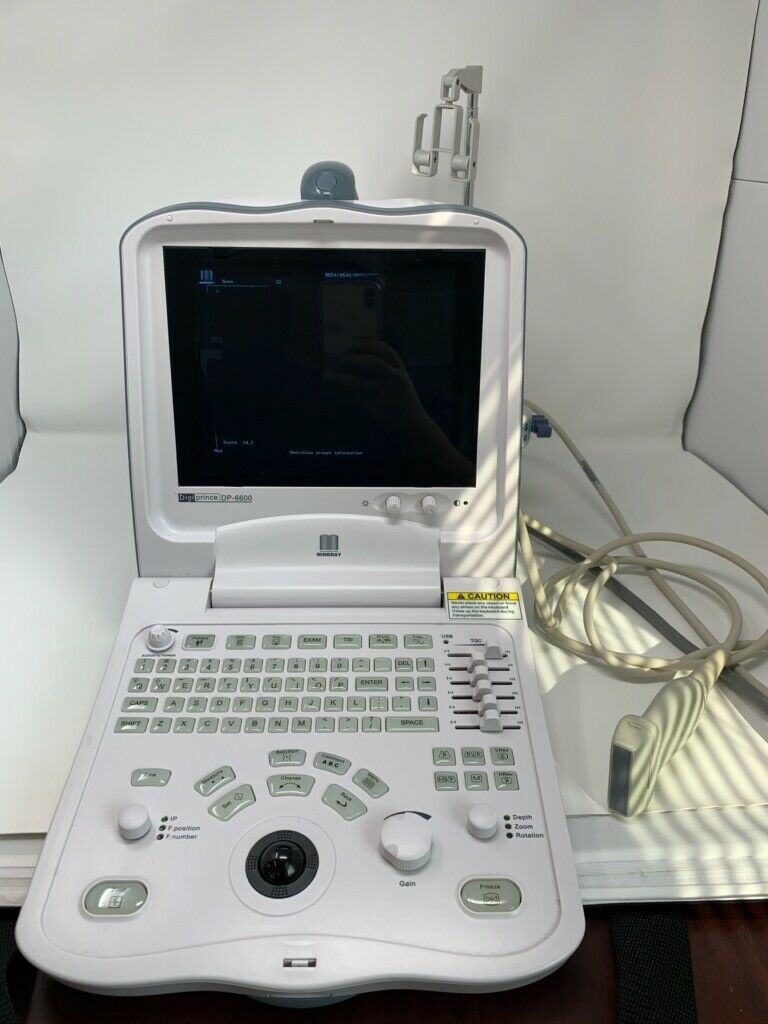

Mindray DigiPrince DP-6600 Ultrasound Machine with Transducer

Sale price$ 10,492.00

Regular price$ 11,192.00

Save $ 350.00